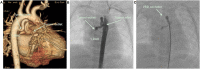

Introduction: Congenital descending aorta-right atrial tunnel is a rare congenital heart defect. Herein, a new case successfully treated by transcatheter closure using a new type of ventricular septal defect occluder from the aortic side was reported. Case Presentation: An 11-month-old Chinese girl presenting with a cardiac murmur was suspected with partial anomalous pulmonary venous connection as assessed by echocardiography. Descending aorta-right atrial tunnel was confirmed by computed tomography angiography and cardiac catheterization. Subsequently, transcatheter closure was performed successfully using a new type of ventricular septal defect occluder from the aortic side. The cardiac murmur disappeared after the intervention, and echocardiography did not reveal any abnormal flow inside the right atrium. At 6 months, the patient had no murmur, and no residual shunt was found using the echocardiogram. Conclusion: Descending aorta-right atrial tunnel is a rare anomaly. Transcatheter closure was successful in our case. Long-term follow-up is needed to assess any progressive growth of the residual tunnel.